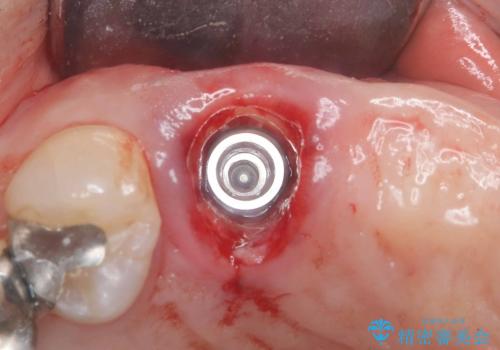

術前のCT画像より、抜歯即時インプラントが可能と判断したため、抜歯と同時にインプラント埋入を行いました。術式にはセミルーナーフラップを用い、唇側の骨吸収を抑える目的でルートメンブレンテクニックを併用しました。

抜歯即時インプラントには、切開量が少なく痛みが出にくいこと、一度の手術で治療が完了するため治療期間を短くでき、患者様の身体的負担も軽減できるという大きなメリットがあります。

今回のケースでも、しっかりと固定が得られたため、手術は1回で終了し、短期間でオールセラミッククラウンまで装着することができました。患者様も術後の痛みはなく、処方した痛み止めも服用されなかったとのことです。